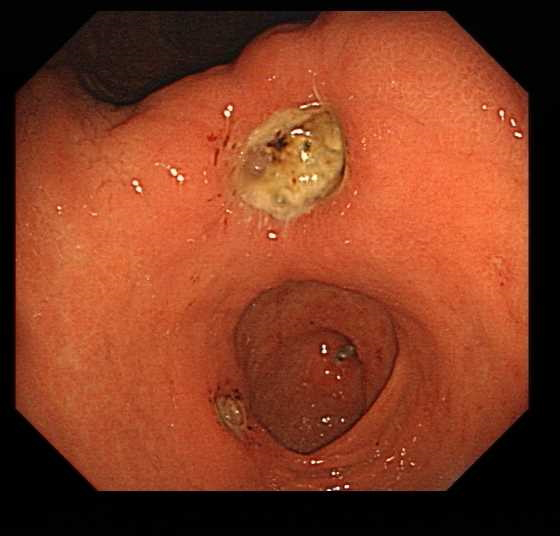

面对金大妈胃中这颗质地坚硬的“金丹”,章医生联合消化内镜团队制定了一套周密的治疗方案。他们使用了多把圈套器,小心翼翼地先将结石捣碎成小块,再逐一取出。

“胃结石的治疗方法多样,主要取决于结石的大小和质地。”章医生介绍,“较小的结石可以通过饮用可乐等酸性液体软化溶解,但像金大妈这种较大且坚硬的结石,往往需要内镜下碎石或外科手术取石。”

整个内镜下治疗过程持续了一个多小时,当最后一块碎石被取出时,医护人员都松了一口气。金大妈胃里的“修真金丹”终于被成功摘除。